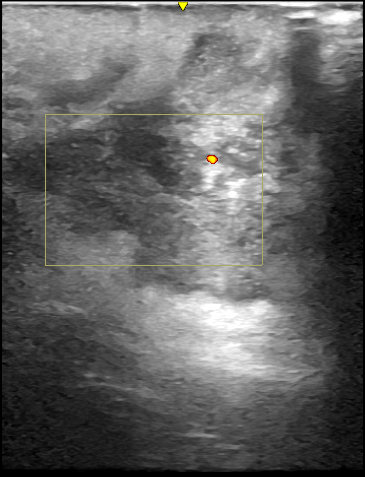

診察時、後頚部に直径80mmの発赤を伴うしこりがあり、超音波検査により典型的な感染性粉瘤と診断されました。一部、僧帽筋筋膜にも炎症が波及していました。採血で糖尿病も認められたため、糖尿病の治療と並行して粉瘤の治療を行う方針となりました。

初回手術術前